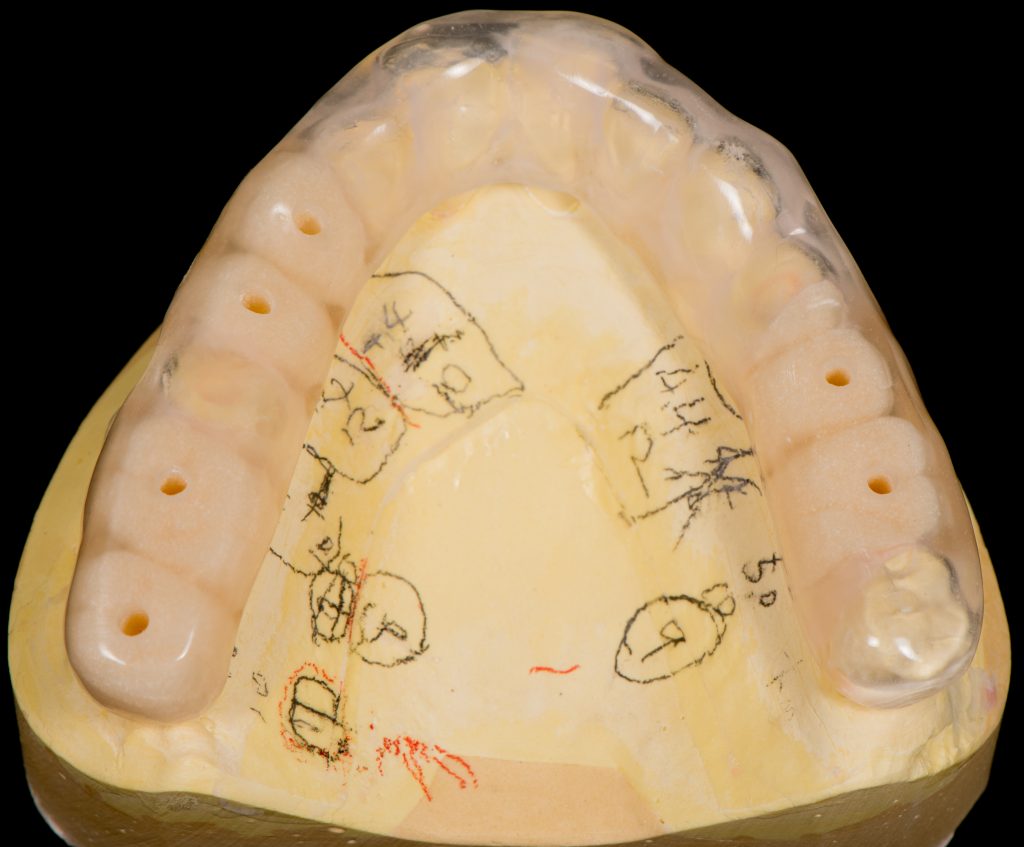

本数が多い為、最終的な歯の位置を考えてインプラントをする必要があります。その為、サージカルガイドと呼ばれる物を作製し、インプラントの位置を決めCT撮影を行いオペを行いました。

サージカルガイド(最終的な歯の位置を考えた設計)

サージカルガイドはインプラントの設計図です

CT画像とサージカルガイドを用いてインプラントの手術を行いました。